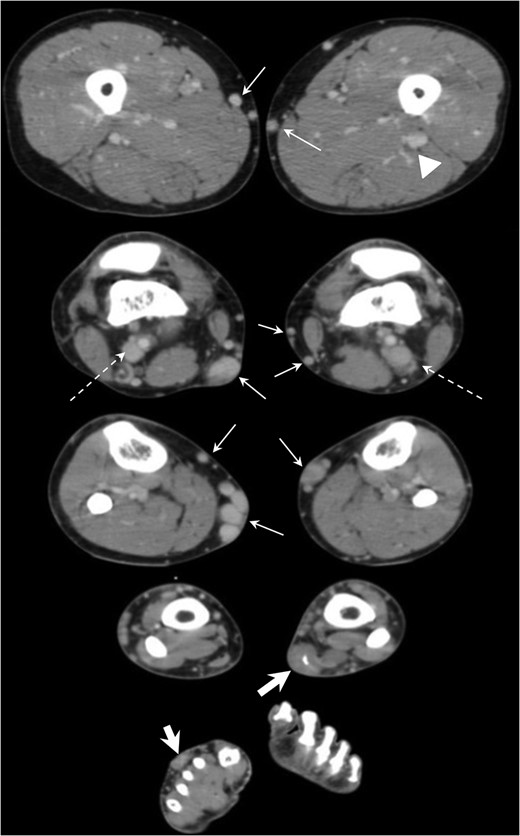

CT venography revealed dilation of superficial veins in bilateral lower limbs (arrows), persistent with the bilateral lateral marginal veins (dotted arrows) and left sciatic vein (arrow head) and soft tissue density area centered in dorsal subcutaneous fat layer of right foot and left lower limb (thick arrows).